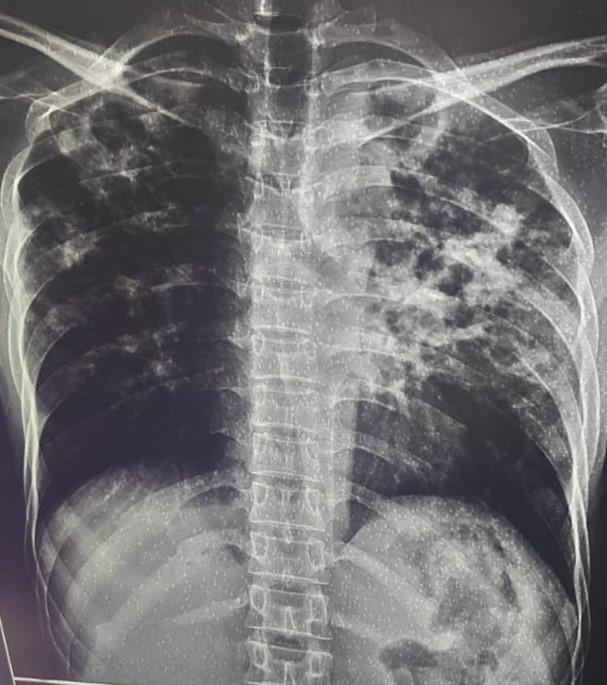

| 340 | IGGMC, Nagpur, Nagpur | P2 | 29-4132 | Ajay Dhabne | Consent taken on Paper | 44 Yrs. |

Provisional Diag : ILD (Interstitial Lung Disease)

Final Diag : ILD In Exacerbation With Old Treated Pulmonary TB With Post Covid Satiation |

Result awaited (Suspected TB/Non-TB) | Abnormality visible on x-ray |